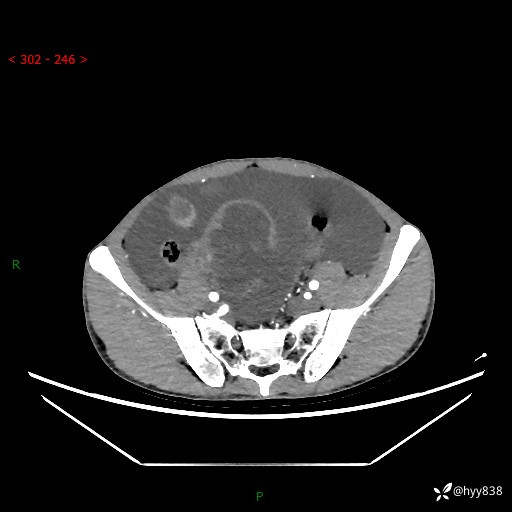

现病史:患者10天前无明显诱因出现腹部胀痛不适,无畏寒发热,无胸痛胸闷,无心慌气短,无恶心呕吐,无腹泻及黑便,无粘液血便及里急后重等症状,4天前在当地县人民医院就诊,行腹部CT示:下腹部占位性病变,腹腔及盆腔积液;今患者为求进一步诊治来我院治疗,门诊以“腹水”收治入院。 发病以来,精神饮食可,大小便正常,体重体力无明显变化。

腹部CT平扫+增强